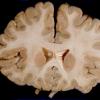

Methylene Blue Treatment